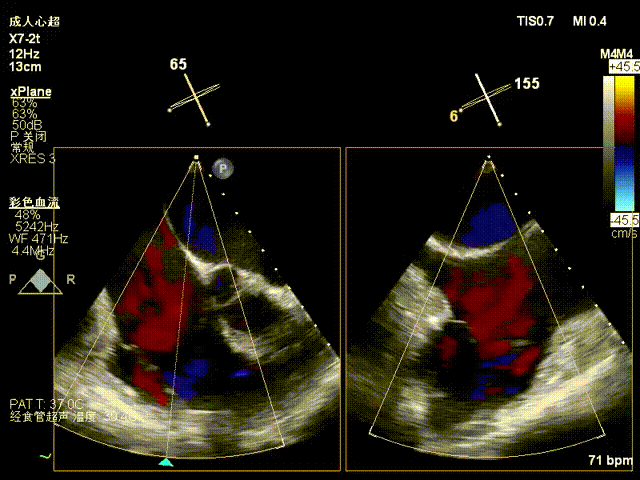

Postoperative regurgitation baseline

Following annuloplasty, leaflet coaptation was improved compared with the preoperative state, and regurgitation was reduced from severe to trivial.

1. The tricuspid annulus was significantly reduced, and the degree of regurgitation was reduced from severe to trivial, with a marked improvement in regurgitation. Although the coronary artery course was somewhat affected intraoperatively, blood supply remained normal. For patients at high coronary risk with concomitant tricuspid regurgitation, the outcome exceeded expectations and successfully alleviated the patient’s burden.